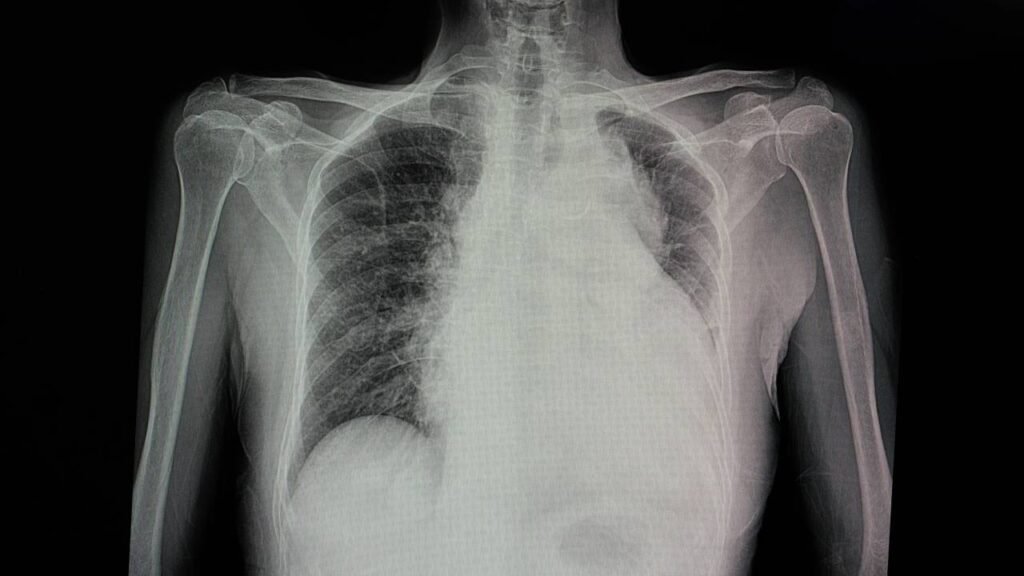

O diagnóstico preciso do Edema Pulmonar é fundamental para o tratamento eficaz e é conduzido normalmente por um pneumologista ou cardiologista. A confirmação da presença de água nos pulmões começa com a análise cuidadosa dos sintomas apresentados. Em seguida, exames de imagem, como o raio-X de tórax, são essenciais para identificar a presença de líquido nos pulmões, mostrando frequentemente uma mancha borrada ao redor das áreas afetadas.

Além do raio-X, exames complementares podem ser solicitados para avaliar a função cardíaca e pulmonar, incluindo eletrocardiograma, tomografia do tórax e gasometria arterial. Esse último exame é fundamental para avaliar a quantidade de oxigênio e dióxido de carbono no sangue, ajudando a identificar a causa do edema.